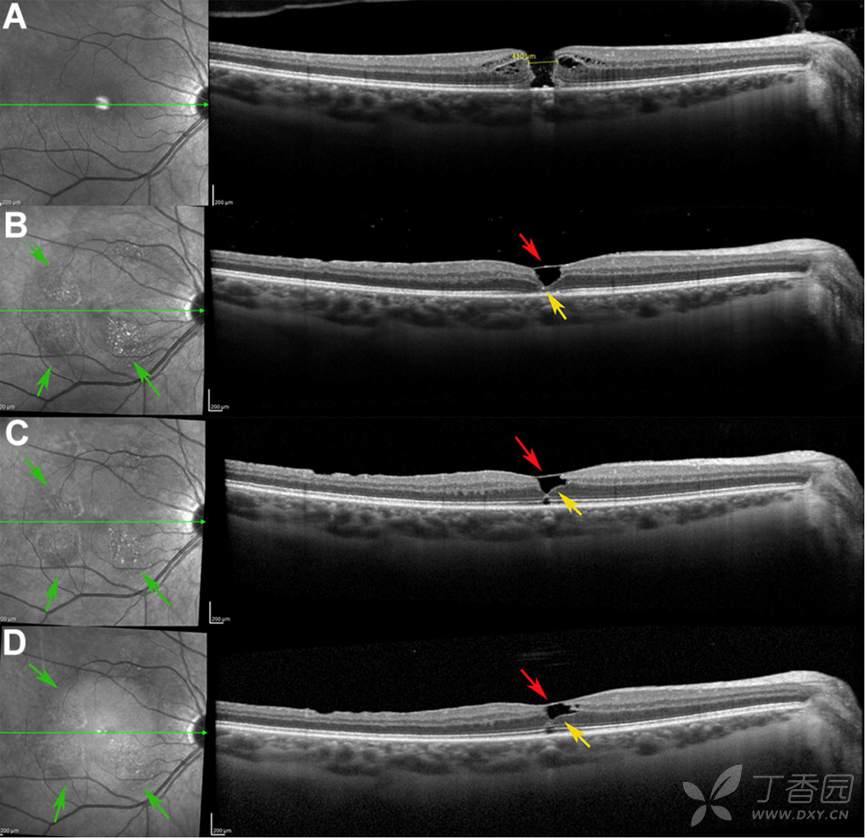

图:术后OCT检查显示内界膜下视网膜组织逐渐填充中心凹(黄色箭头)

图:无赤光眼底照相显示术后黄斑区域视网膜向心性移位(红色箭头为术前,黄色箭头为术后)